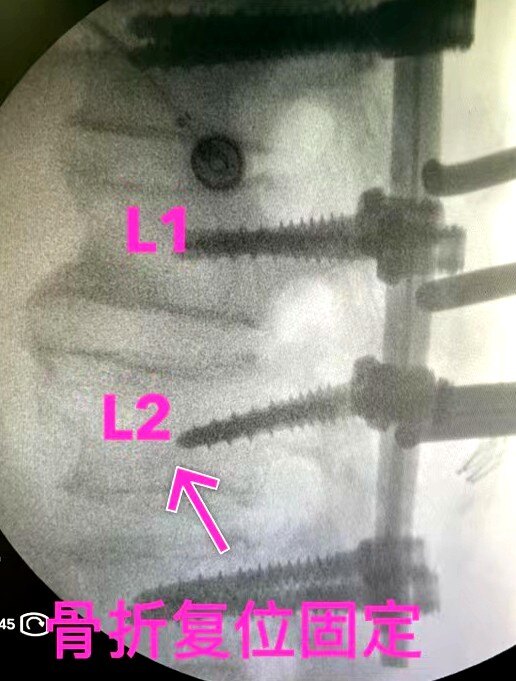

术后:骨折复位固定、脊柱序列恢复、椎管减压良好